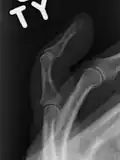

- Un doigt en maillet sans fracture associée